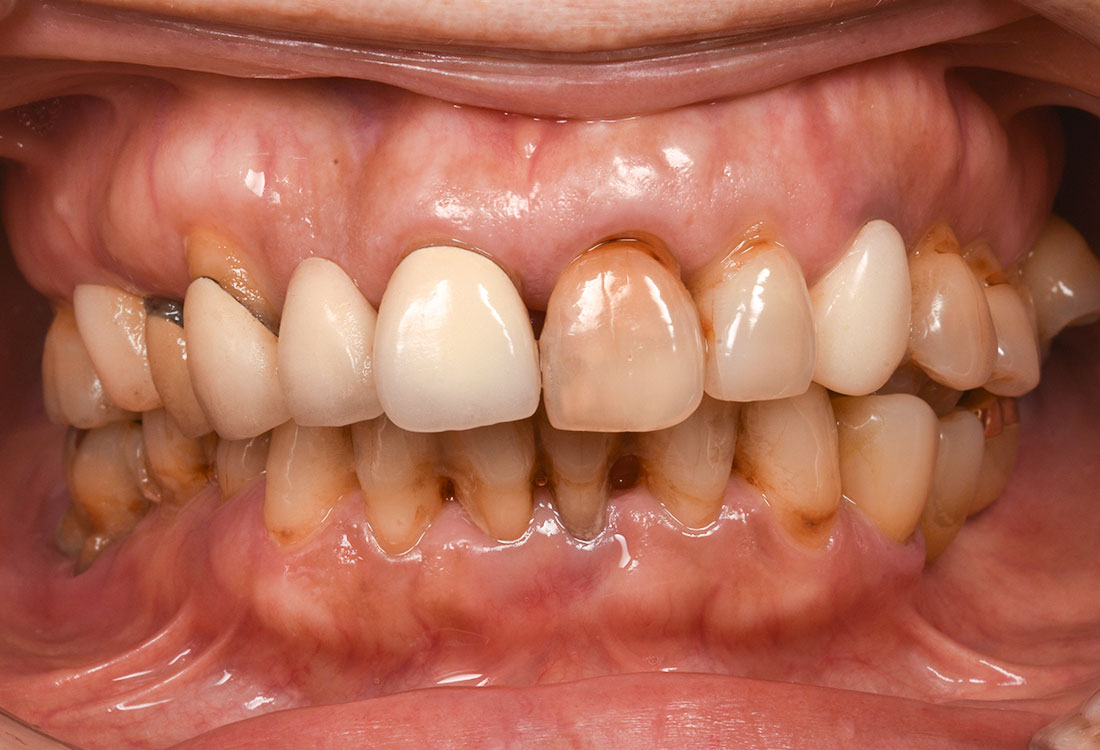

ご相談内容

- 歯並びが気になる

- 矯正をする時間が取れないので被せ物で治していきたい

治療前